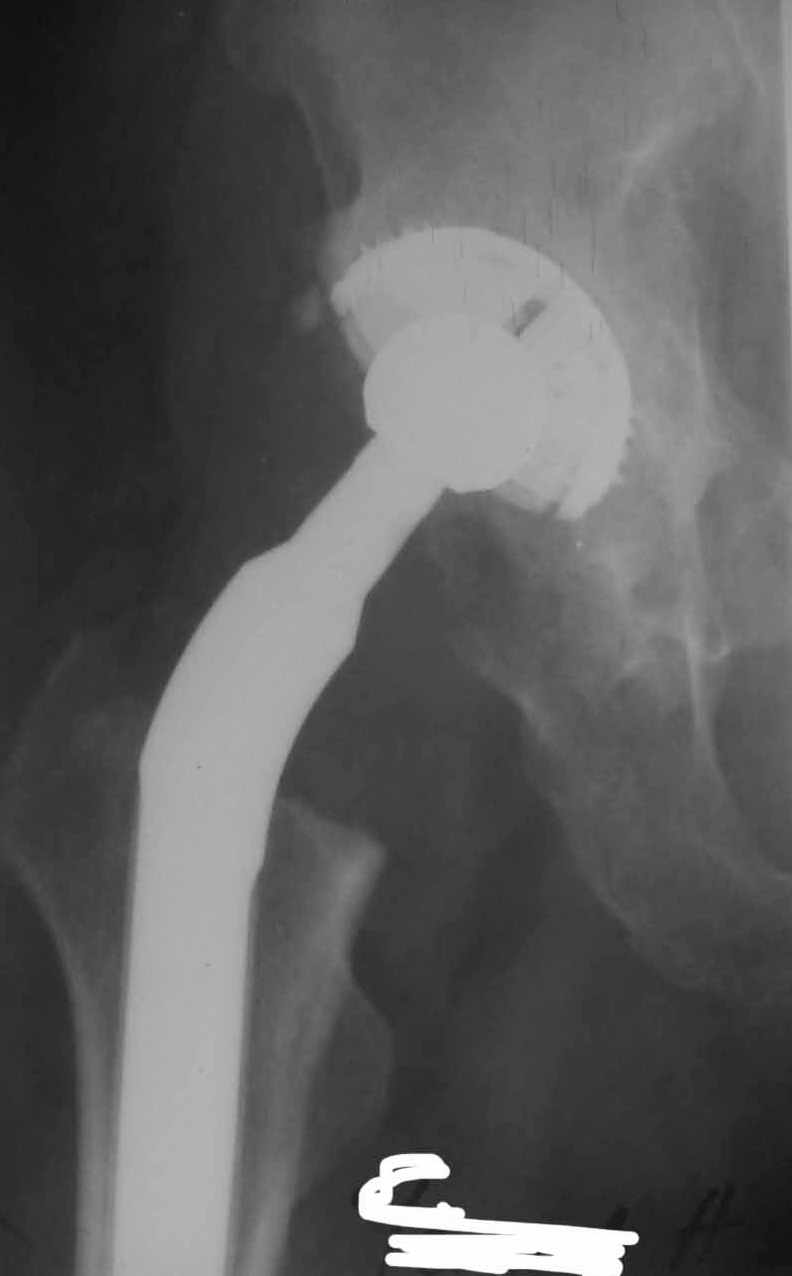

1. Ревизия безотлагательно.

2. Вывихивание протеза, снятие головки

3. Экстракция ножки до уровня, когда ее диаметр станет меньше, чем

диаметр посадочного места в канале бедренной кости.

4. Внутренняя ротация ножки на 1-2 насечки (они есть на ножке Вагнера и довольно хорошо позволяют ориентироваться - это около 10-20 град), т.к. проблема именно в том, что ножка установлена с

ошибочно заданным углом антеверсии и, скорее всего, с избыточным удлинением - именно это мы и увидим на передне-задней рентгенограмме(!) таза.

5. Мощное медикаментозное прикрытие операции (тиенам, клексан(фраксипарин, фрагмин), липостабил, антиагреганты).

К сожалению, подобные ситуации я уже проходил лет 8-10 назад лично, а сообщество хирургов, занимающихся эндопротезированием, сделало давно

однозначный вывод о тактике - активное вмешательство для разрешения проблемы. Сам-то протез на место не встанет!

Здесь я позволю себе с Вами не согласиться. Мне кажется, что прав коллега Тихилов - объем резекции большого вертела кажется избыточным.

Надо попробовать активизировать больного, разрешить ему ходить с нагрузкой до 50% веса тела, сидеть.

Оперировать только в случае повторного вывиха.